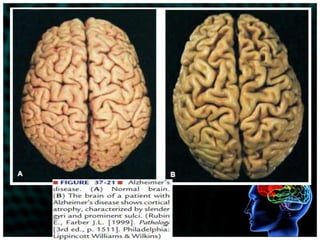

Gross pathophysiologic changes:cortical atrophyenlarged ventriclesbasal ganglia wastingMicroscopically:Changes in the proteins of the nerve cells of the cerebral cortexaccumulation of neurofibrillary tangles and neuritic plaques (deposits of protein and altered cell structures on the interneuronal junctions) granulovascular degenerationloss of cholinergic nerve cells (important in memory, function, cognition)

Gross pathophysiologic changes:corticalatrophyenlarged ventriclesbasal ganglia wastingMicroscopically:Changes in the proteins of the nerve cells of the cerebral cortexaccumulation of neurofibrillary tangles and neuritic plaques (deposits of protein and altered cell structures on the interneuronal junctions) granulovascular degenerationloss of cholinergic nerve cells (important in memory, function, cognition)